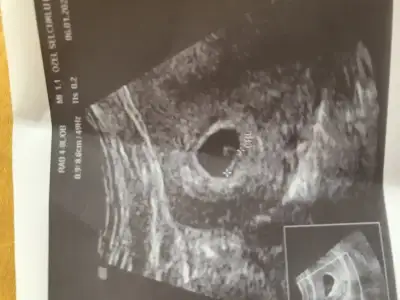

Merhaba. 6 haftalık karından ultrason fotoğrafı bu tahmini olan varmı?

Eklentiler

• 20200115_104527-1-1.webp

20200115_104527-1-1.webp

19,6 KB · Görüntüleme: 110